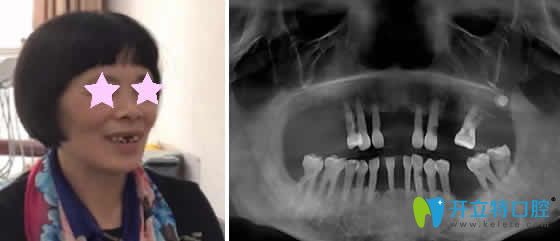

重慶華諾世口腔怎么樣?看李清醫(yī)生微創(chuàng)即刻種植牙案例效果圖:

種植牙前:上邊門牙兩邊牙齒缺失,吃飯困難。

種植牙后:即刻種植牙當(dāng)天回家能啃蘋果,而且自然美觀。